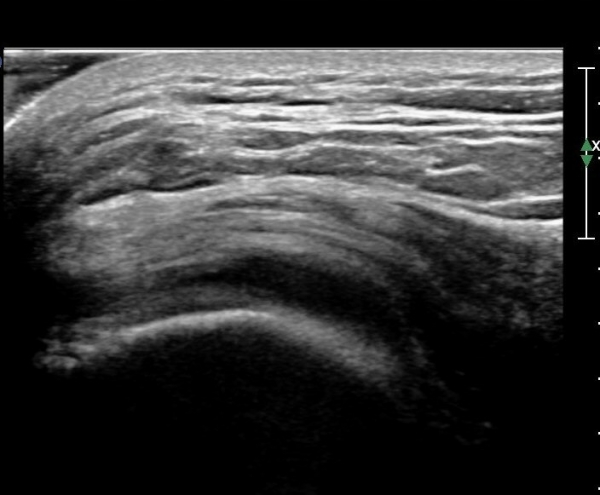

ŽÃËÀÚ¸¦ ¾ÕÂÊÀ¸·Î À̵¿ÇÏ¿© ´ëÀüÀÚ ¾ÕÂÊ È¾´Ü¸é°Ë»ç¿¡¼­ ¼ÒµÐ±ÙÈûÁÙ°ú Àå°æÀÎ´ë »çÀÌ¿¡

¼Ò·®ÀÇ ¼ö¾×Àú·ù°¡ °üÂûµÇ°í(»çÁø 4)